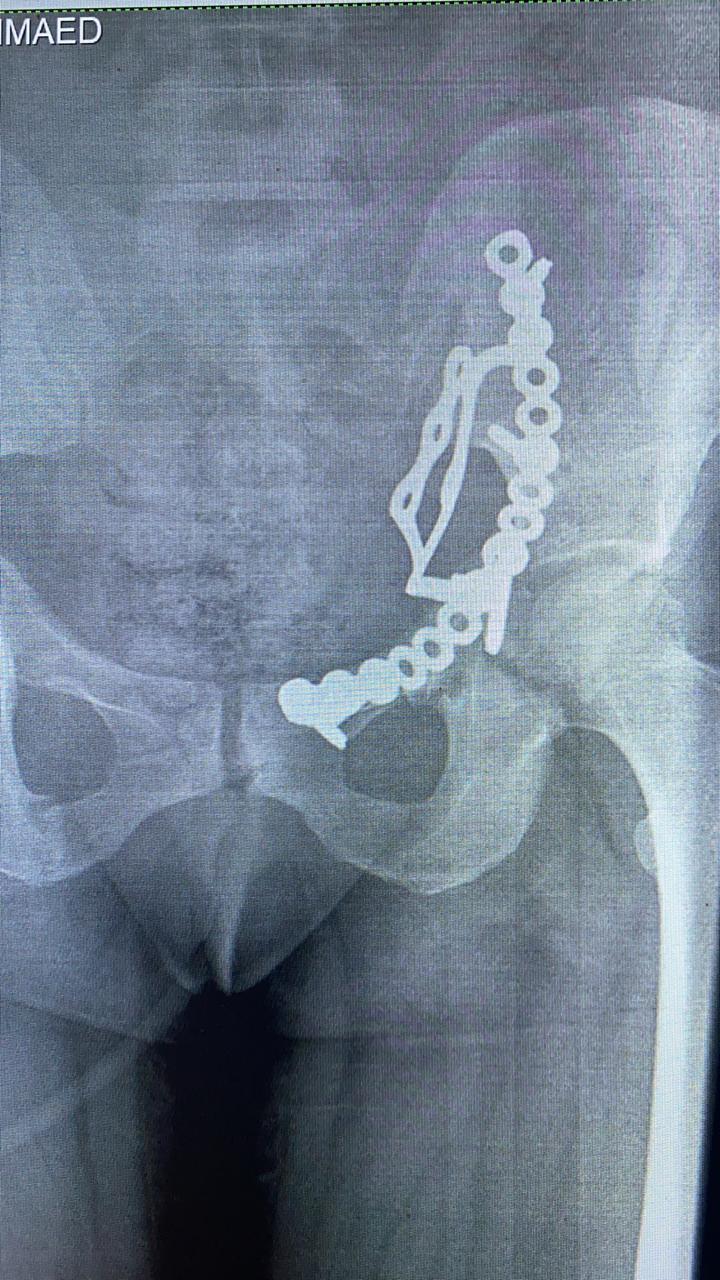

وأوضح وكيل الوزارة، في بيانٍ له، قبل قليل، أنه تم إجراء عملية إصلاح الكسور المتعددة المفتتة بعظام الحوض للسيدة تحت إشراف مدير مستشفى أبو حماد المركزي، إذ تم إجراء عملية رد مفتوح مع تثبيت داخلي لكسر مفتت بالحق الحرقفي لـ عظم الحوض للسيدة، وذلك من خلال جراحة فتح البطن والحوض باستخدام شريحة من نوع خاص تحت مُخدر عام بغرفة العمليات بمستشفى أبو حماد المركزي.

وأشار وكيل وزارة الصحة بمحافظة الشرقية، إلى أن العملية التي أجريت تُعد ذات طابع خاص، وذلك بعد دخول المريضة قسم الاستقبال والطوارئ بمستشفى أبو حماد المركزي، إثر ادعاء حادث مروري، منوهًا بأنه تم إجراء كافة الفحوصات اللازمة، وتبين إصابة المريضة بجرح بالمثانة نتج عنه بول دموي ووجود كسر مفتت بالحق الحرقفي لعظم الحوض، قبل أن يشير إلى إجراء العملية، وأن المريضة الآن في حالة جيدة ومستقرة تحت متابعة الأطباء بمستشفى أبو حماد المركزي.